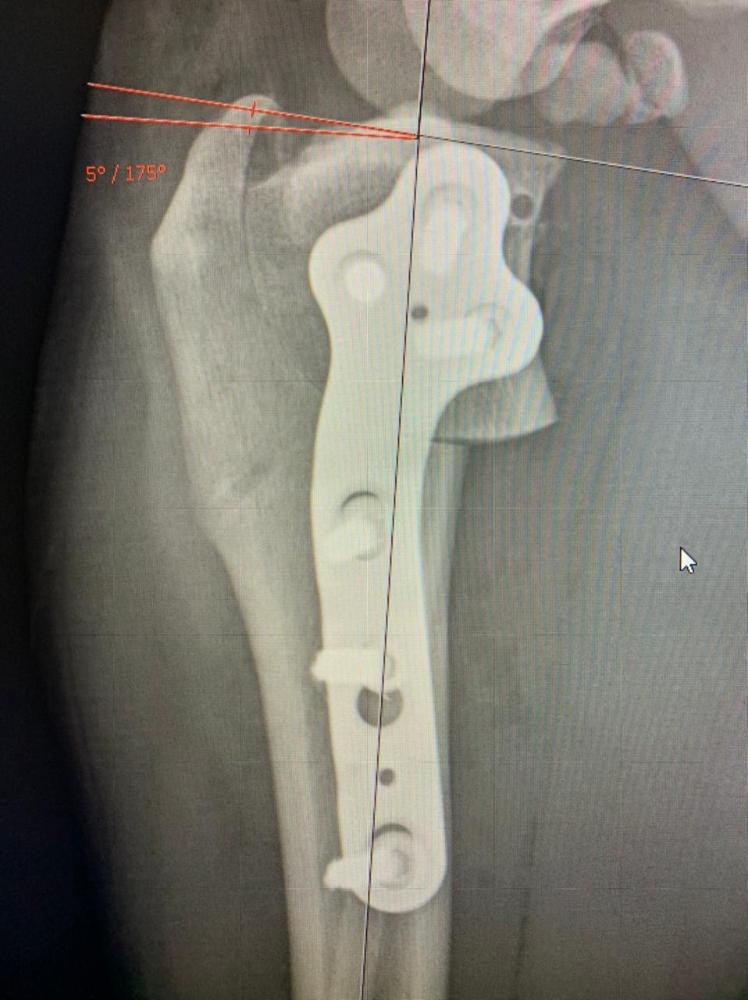

Бэкки Опубликовано 19 февраля, 2021 Опубликовано 19 февраля, 2021 Ну вот мы и дома! Ходит пока на 3 лапках, на лапе, которую оперировали компрессионная повязка, которую не снимать до вс, в воскресенье на приём к хирургу, снимут повязку. Катетер тоже оставили, до завтра, если будет нормально кушать и гулять, завтра снимем. Чувствует себя вроде нормально, покушала и легла спать. Воротник, естественно, жутко не нравится. Пока как-то так. Снимки рентгена: 1 7